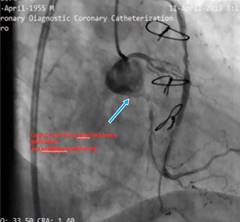

The patient was a 78 years old male with a history of CABG and PCI. His medical history included hypertension, hyperlipidemia and a previous PCI on the SVG to the obtuse marginal (OM) artery (Figure 1).

Figure 1: Thrombotic SVG with in-stent restenosis LCx CTO from ostial with no antegrade guide support. (J CTO Score; 4 Long, Calcified, Ambiguous proximal CAP and retry).

The patient presented with symptoms of acute coronary syndrome, including chest pain and shortness of breath. The ECG was in sinus rhythm and q wave was seen in D2, D3 and AVF leads. (Figure 2) His blood tests showed no significant values. He was referred to our center for tertiary care after coronary angiography performed at another hospital revealed a thrombotic SVG with in stent restenosis and CTO of the left circumflex artery (LCx) (Figure 3).